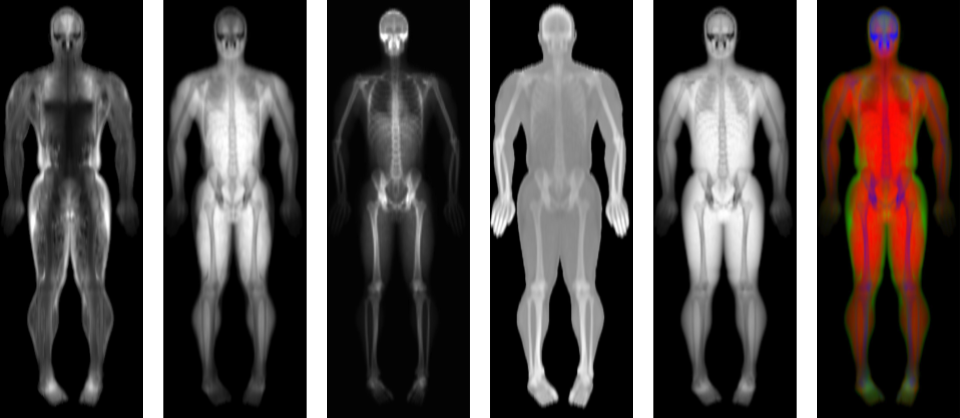

We’ve all heard about Body Mass Index (BMI), but did you know it’s a pretty basic measure? BMI only considers your weight and height, missing crucial details like muscle mass, bone density, and fat distribution. Enter Dual-energy X-ray Absorptiometry (DEXA), a game-changer that provides a detailed breakdown of your body composition.

DEXA scans use low-dose X-rays to measure different energy levels passing through your body, giving us a clear picture of muscle mass, visceral fat, subcutaneous fat, and bone mass. This detailed information helps us understand how your body composition affects your health and longevity.

Research has shown that body composition is a strong predictor of health outcomes. For example, the Health, Ageing, and Body Composition study revealed that changes in muscle mass, bone density, visceral fat, and weight over time can indicate health risks. But here’s where it gets exciting—AI can now analyse DEXA scan images directly, using all the raw data to make even more accurate predictions about your health.